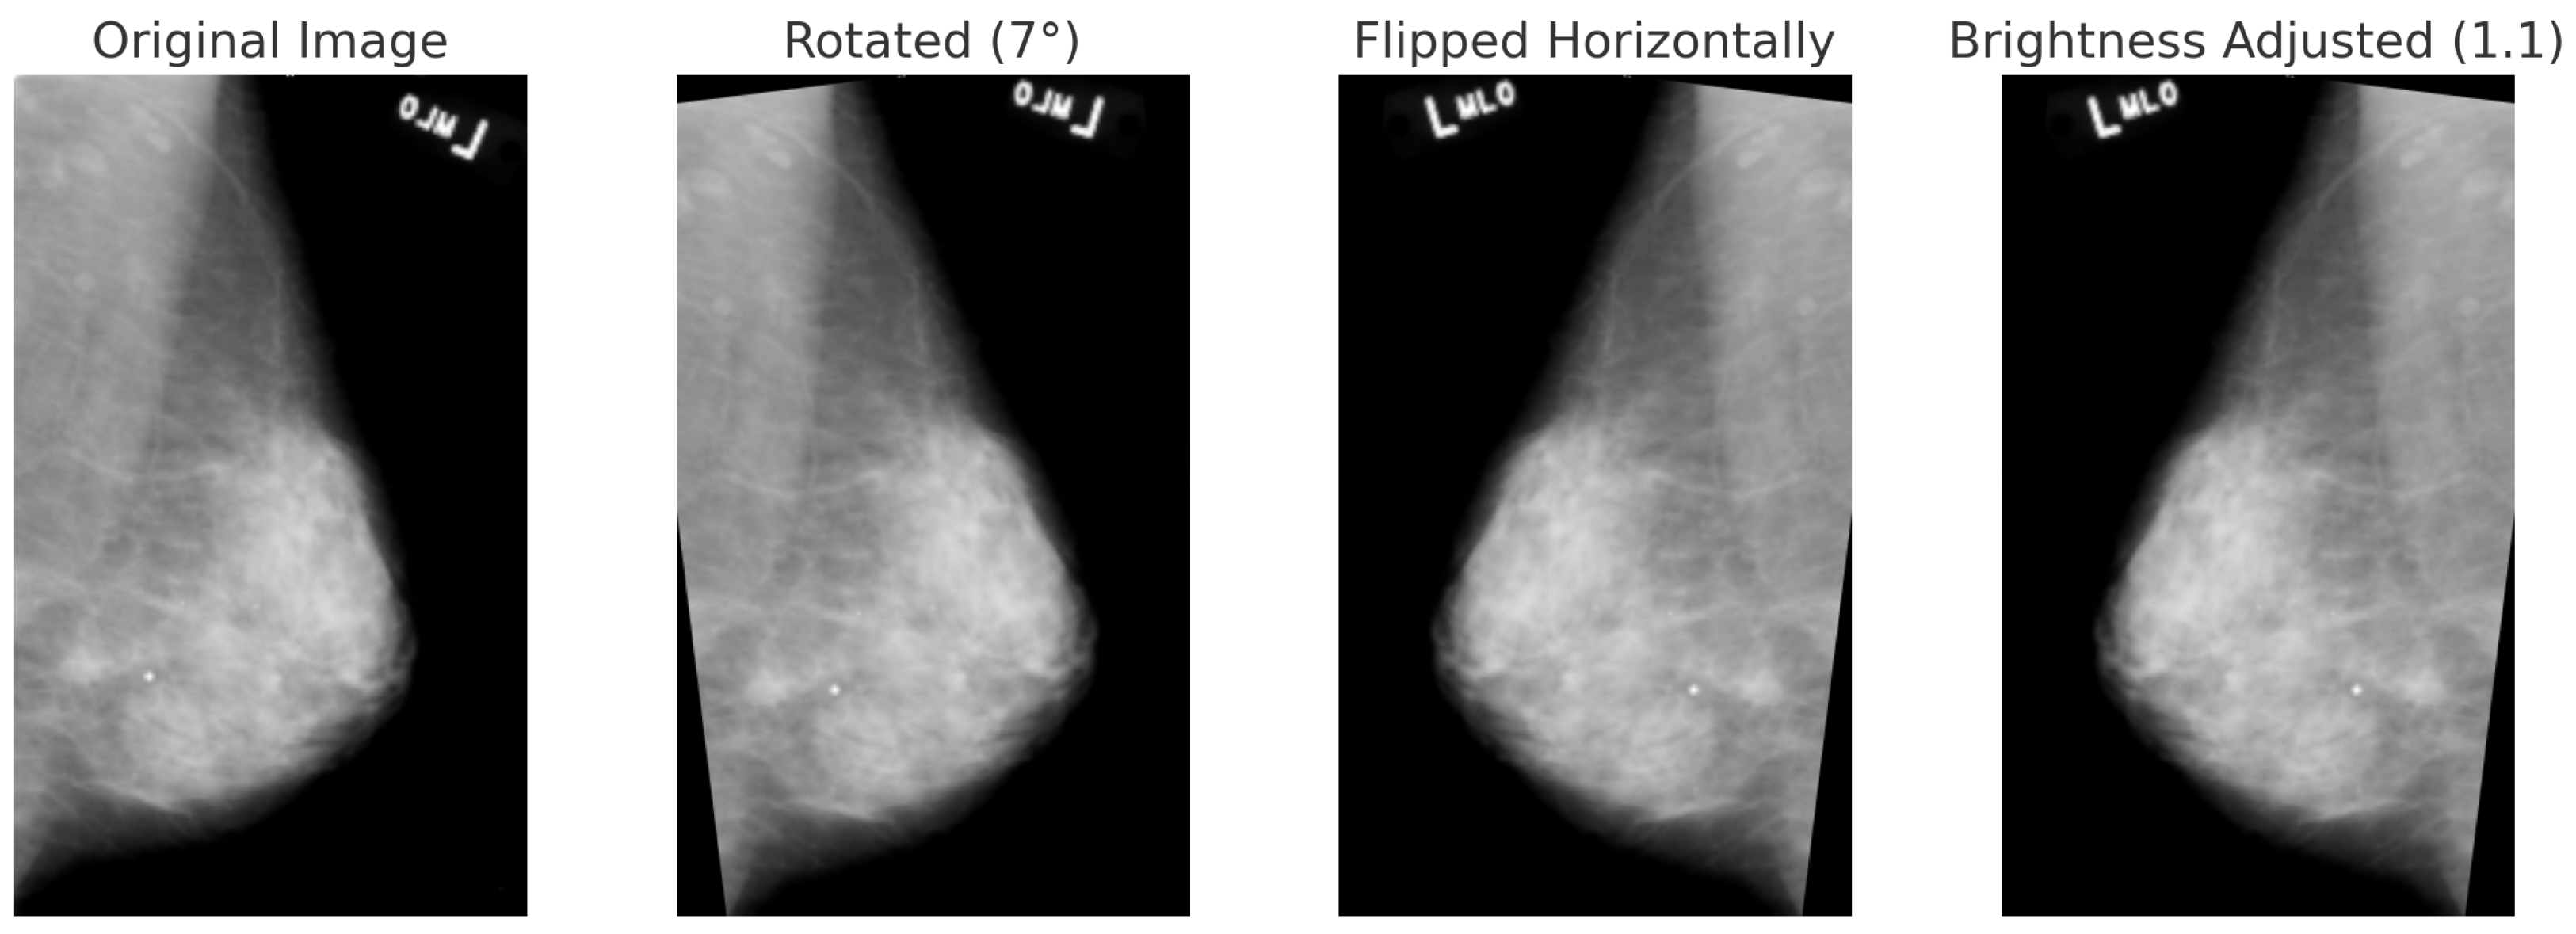

For BreakHis, extensive geometric (rotation ± 20°, flips) and photometric (zoom, brightness) transformations were applied to reflect slide orientation variability and staining inconsistencies. BUSI employed elastic deformation, speckle noise, and contrast adjustment to mimic tissue distortion and signal artifacts. INbreast received conservative adjustments to enhance tissue visibility without losing diagnostic fidelity. CBIS-DDSM used mild rotation, flipping, and brightness changes, maintaining lesion structure integrity. The Combined Dataset integrated harmonized augmentations from all sources, ensuring cross-modality consistency while retaining BUSI-specific elastic transformation. The chosen values prioritize generalization while preventing excessive transformations that could alter pathological features or diminish diagnostic relevance. Figure 6, Figure 7, Figure 8 and Figure 9 illustrate sample images from each dataset after the application of these data augmentation techniques.

Each dataset undergoes an 80:5:15 stratified split to maintain class balance across the different partitions. Table 4 outlines the dataset-specific augmentation strategies employed in this study. The parameters were selected based on typical acquisition conditions and the visual characteristics of each modality, ensuring that the transformations are clinically reasonable. By introducing controlled variations, this strategy enhances the model’s robustness against both intra-dataset variability and inter-dataset domain shifts. This approach particularly benefits the performance of minority classes while preserving anatomical fidelity.